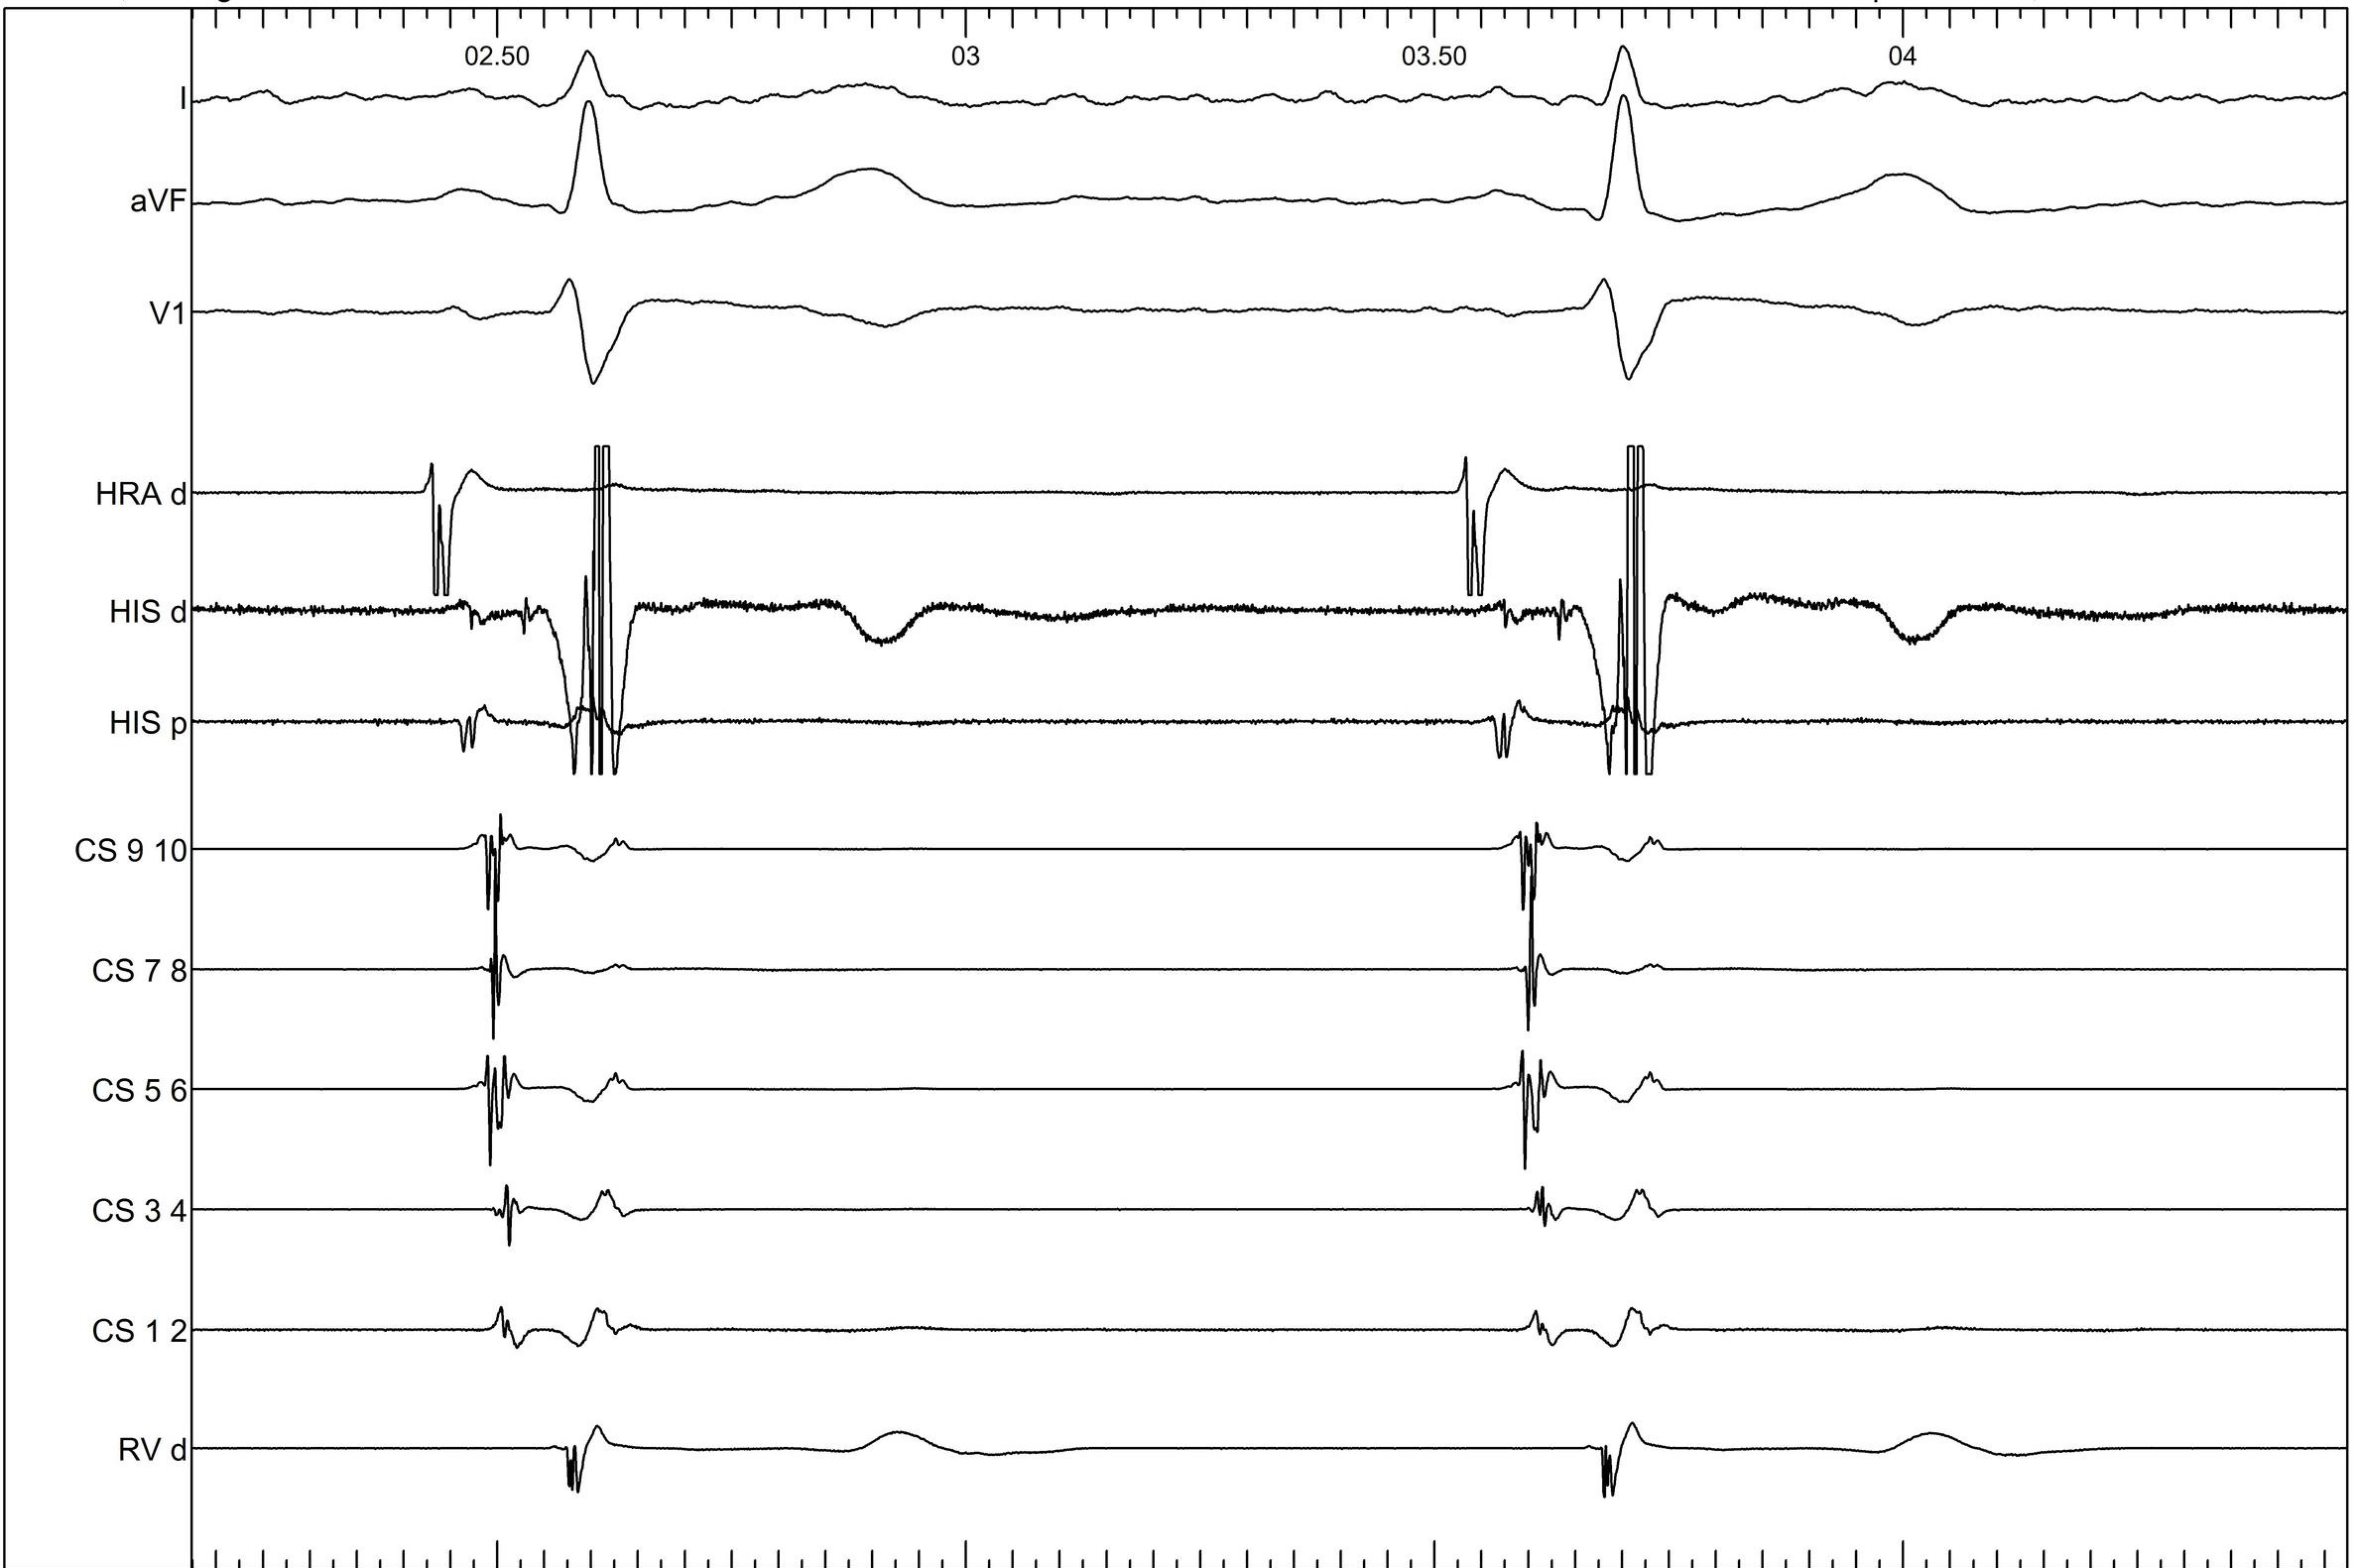

Ventricular extrastimulus

03_v_extra.jpg

Ventricular extra

07_v_extra_tachy.jpg

Where do you want to map